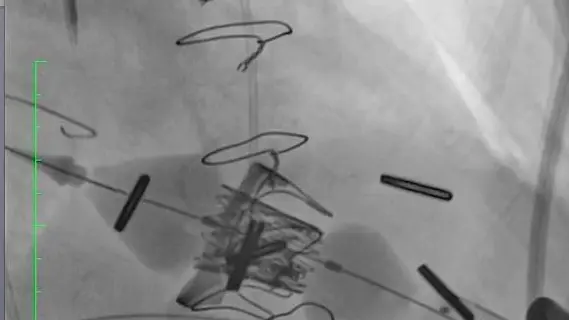

Consiste nell'impianto di una nuova bioprotesi all'interno di quella vecchia e malfunzionante attraverso una piccola incisione laterale del torace di 5-6 centimetri e dell’apice cardiaco (nella figura 3 l’incisione del torace e nella 4 l’impianto della nuova bioprotesi).